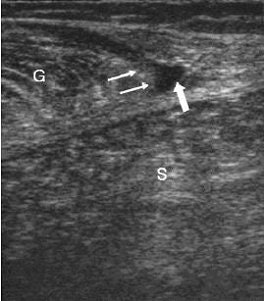

MR images of the tennis leg injury sustained by Mintz. Above, a coronal fat-suppressed image through the back of the calf with the arrow pointing to the muscle tear. The hematoma is tracking up the leg. Below, sagittal MR of the whole calf. Arrow points to the muscle tear and the white below it is the gap from the muscle retraction. Images courtesy of Dr. Douglas Mintz.